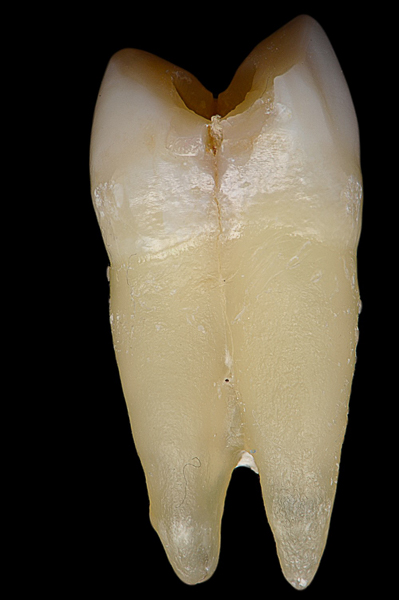

Il caso presenta la riabilitazione di un premolare superiore interessato dal fallimento di un trattamento endodontico in una paziente donna di 37 anni, non fumatrice e con una buona igiene.

Donna, 37 anni, non fumatrice, con una buona igiene, si presenta in studio con un fallimento del trattamento endodontico dell'elemento 1.4.